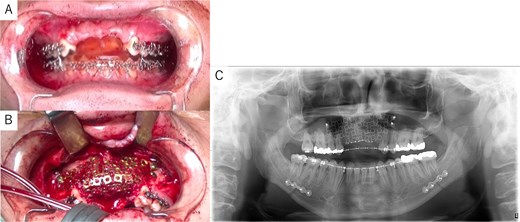

Intraoperative and postoperative images. (A) SSRO surgery was performed with conformity to the orthodontist-prepared final splint. (B) PCBM was grafted into the bone defect and covered with titanium mesh. (C) Postoperative panoramic radiograph showed no abnormalities.

Simulation of dental implant placement in the maxillary anterior region using coDiagnostiX® (Straumann, Basel, Switzerland) revealed insufficient bone volume in both height and width (Fig. 3A). A 3D simulation was performed for bone augmentation in the maxillary anterior region alongside posterior mandibular movement. Mandibular retraction measured 6.2 mm on the right side and 7.0 mm on the left side. DICOM files from dental cone-beam computed tomography were converted to Standard Tesselation Language (STL) data using Volume Extractor® (Volume Extractor 3.0; i-Plants Systems Corporation, Iwate, Japan) (Fig. 3B). Osteotomy lines and the required bone augmentation were established using Geomagic Freeform® (3D Systems, Rock Hill, SC, USA) (Fig. 3C). A 3D model was printed (Straumann® CARES® P20+; Straumann, Basel, Switzerland) from the STL data, and a titanium mesh (Universal Mesh; Stryker Japan, Tokyo, Japan) was shaped to maintain space for PCBM grafting (Fig. 3D). The planned augmentation volume for implant placement was 5.6 mL, with a target bone harvest volume of 9 g, sourced from the right anterior iliac crest. In October 2023, SSRO and bone augmentation were performed simultaneously as planned (Fig. 4A). After harvesting PCBM from the right anterior iliac crest, SSRO was completed. The harvested PCBM was grafted into the bone defect and secured with the pre-bent titanium mesh (Fig. 4B). The wound was sutured, concluding the first operation.